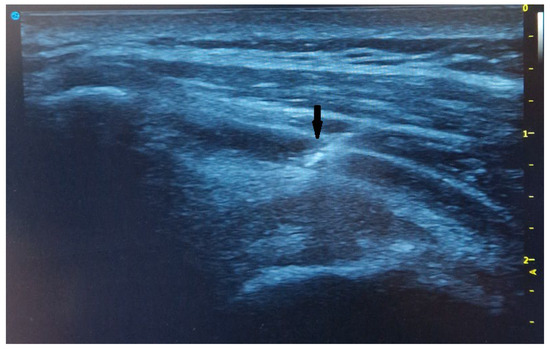

3.5. Tendon Sample Harvesting